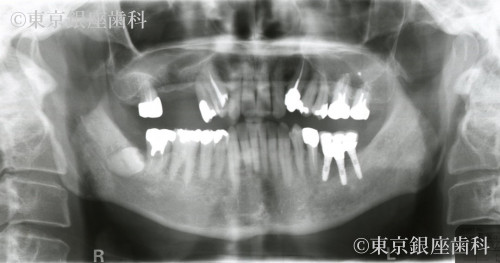

他院で行った2本のインプラント埋入手術とサイナスリフトが原因で入院を伴う上顎洞炎になった。そのインプラントも1年ほどで脱落し再度手術するも固定せず脱落。紹介を受けて転院することになった。

当院来院時にはインプラント除去した部位の粘膜も落ち着いていて義歯を使用できていた。

右上4番の動揺があり予知性が低いため同意を得て抜歯。サイナスリフトを併用した2本のインプラント埋入で右上456番の3本の補綴を行う事とした。